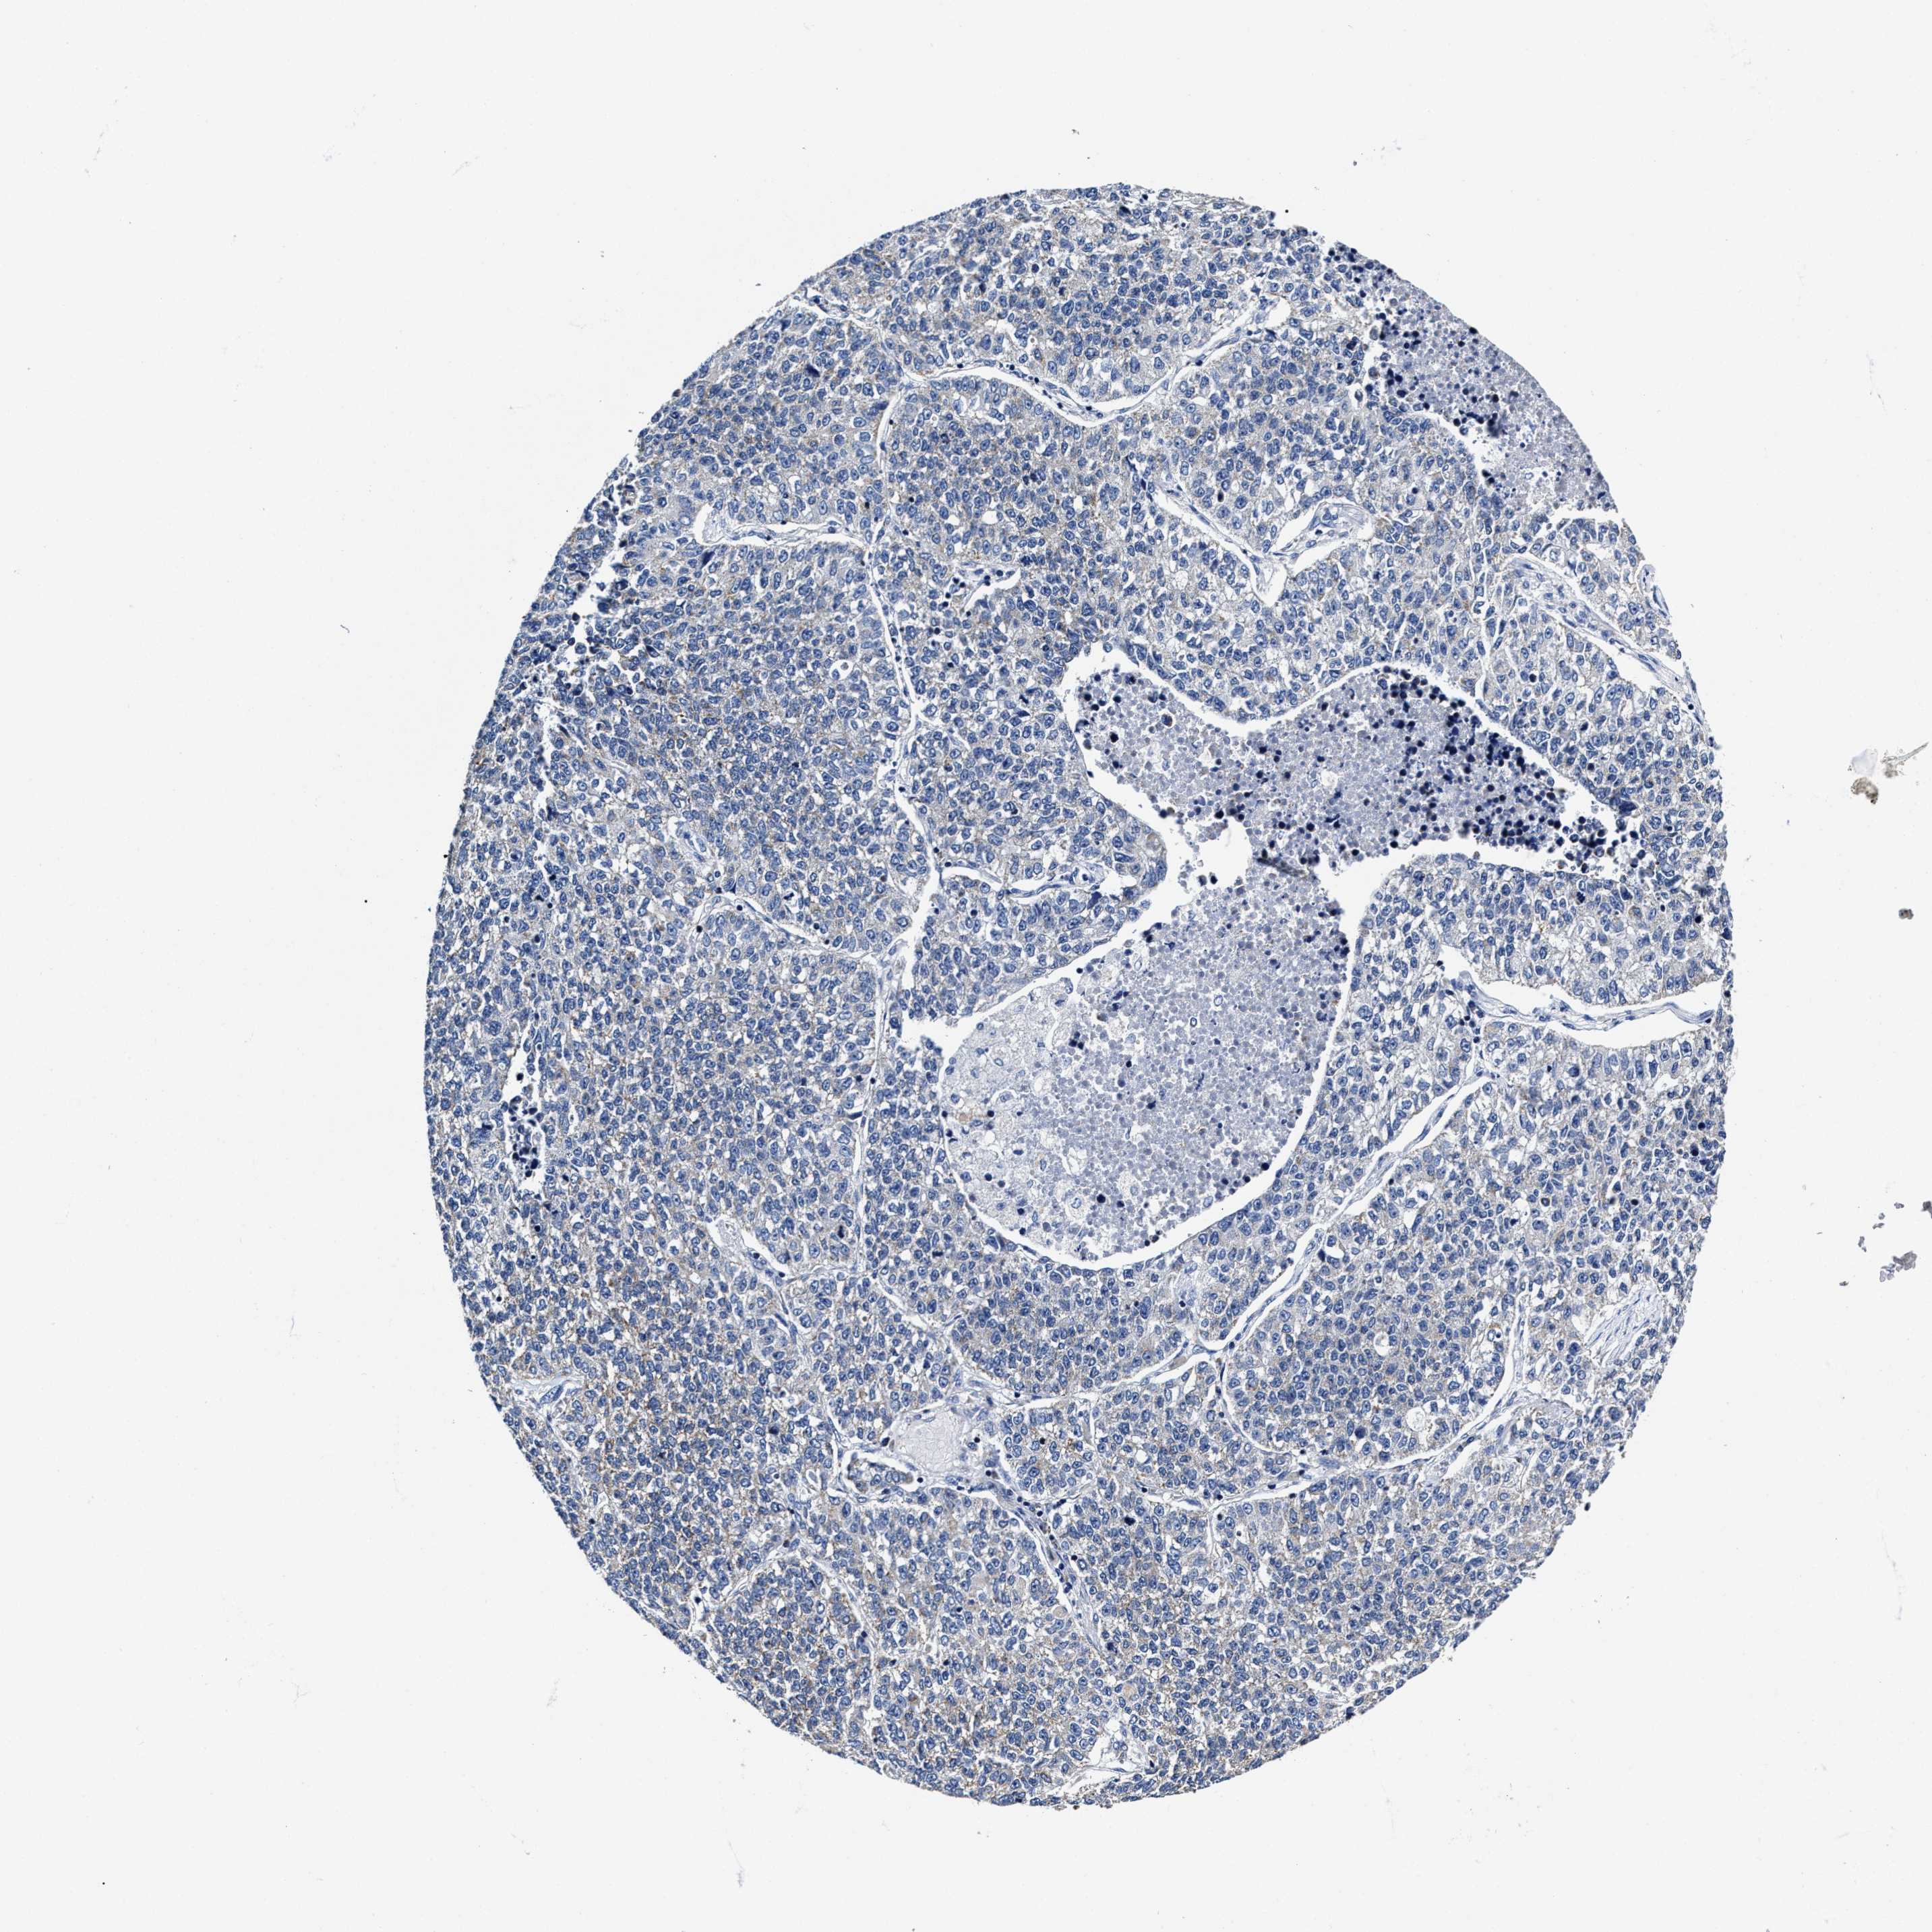

LUNG SQUAMOUS CELL CARCINOMA (TCGA) - Interactive survival scatter ploti

The Survival Scatter plot shows the clinical status (i.e. dead or alive) for all individuals in the patient cohort, based on the same data that underlies the corresponding Kaplan-Meier plots. Patients that are alive at last time for follow-up are shown in blue and patients who have died during the study are shown in red.

The x-axis shows the expression levels (FPKM) of the investigated gene in the tumor tissue at the time of diagnosis. The y-axis shows the follow-up time after diagnosis (years). Both axes are complimented with kernel density curves demonstrating the data density over the axes. The top density plot shows the expression levels (FPKM) distribution among dead (red) and alive patients (blue). The right density plot shows the data density of the survived years of dead patients with high and low expression levels respectively, stratified using the cutoff indicated by the vertical dashed line through the Survival Scatter plot. This cutoff is automatically defined based on the FPKM cutoff that minimizes the p-score. The cutoff can be changed by dragging the vertical line or by entering a cutoff value in the square labeled "Current cut-off".

Under the Survival Scatter plot the p-score landscape (black curve; left axis) is shown together with dead median separation (red curve; right axis). Dead median separation is the difference in median mRNA expression between patients who have died with high and low expression, respectively. It is calculated as follows: median FPKM expression of dead patients with high expression - median FPKM expression of dead patients with low expression. This is intended to aid the user in visually exploring custom cutoffs and the associated p-scores and dead median separation.

Individual patient data is displayed and can be filtered by clicking on one or more of the category buttons on the top of the page. Categories describing expression level and patient information include: high, low, alive, dead, female, male and tumor stages. The scale of the x-axis can be toggled between linear and log-scale by clicking on the "x log" button. Mouse-over function shows TCGA ID, patient information and mRNA expression (FPKM) for each patient.

& Survival analysisi

Kaplan-Meier plots summarize results from analysis of correlation between mRNA expression level and patient survival. Patients were divided based on level of expression into one of the two groups "low" (under cut off) or "high" (over cut off). X-axis shows time for survival (years) and y-axis shows the probability of survival, where 1.0 corresponds to 100 percent.

HINT2 is not prognostic in Lung Squamous Cell Carcinoma (TCGA)

: 28.23

P scorei

N/A

Average pTPM 51.7

Number of samples 489